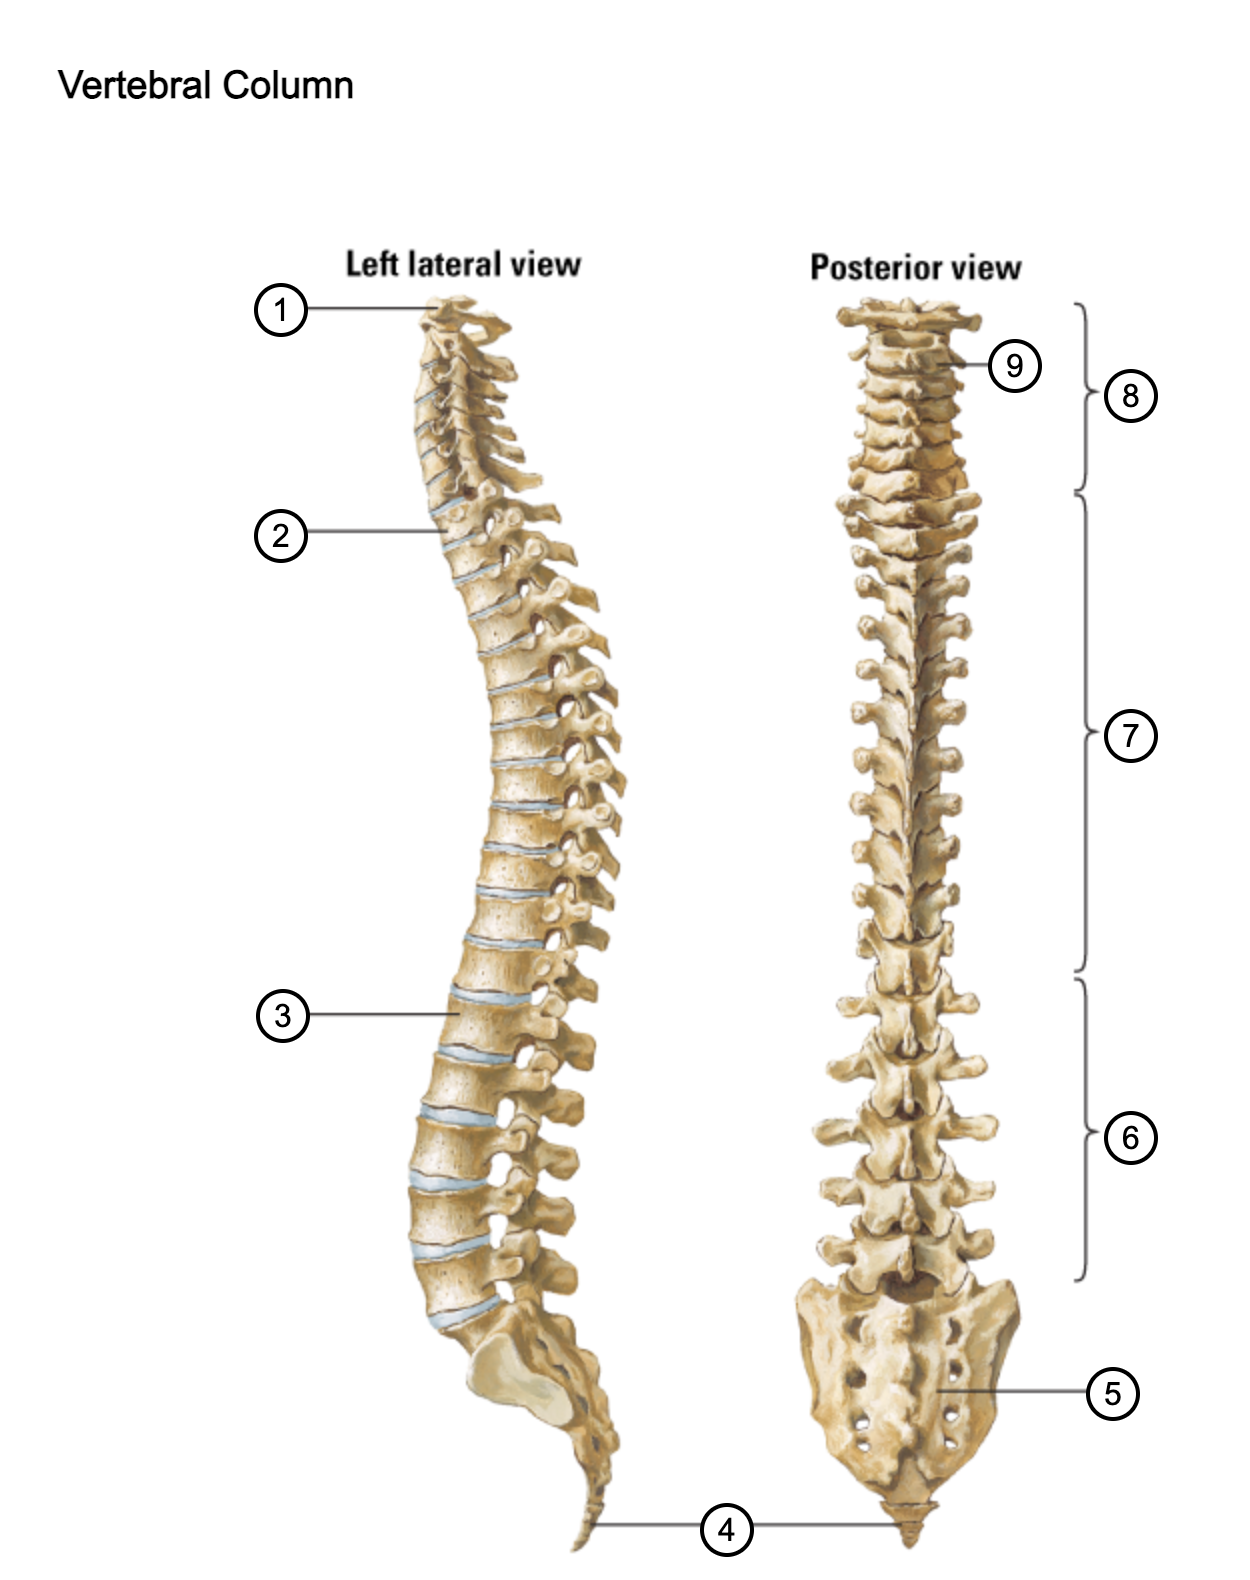

1

atlas (C1)

2

T1

3

L1

4

coccyx

5

sacrum (S1-5)

6

lumbar vertebrae

7

thoracic vertebrae

8

cervical vertebrae

9

axis (C2)